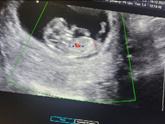

Пока все хорошо, срок по месячным 12нед.6дн. А по УЗИ 12 нед.1день.

КТР 56мм

ЧСС 157 уд.мин

ТВП 1,5

Пол девочка ?? второй врач уже говорит ☘️

Ждём нашу крошку❤️

УЗИ ?

КТР 43мм

Сердцебиение 169уд.мин

Пол девочка ? предположительно ?